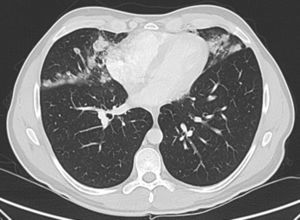

Se solicitó radiografía de tórax posteroanterior y lateral y posteriormente tomografía computarizada (TC) de tórax, que mostró la presencia de nódulos irregulares (acinares), e infiltrados alveolares en lóbulo medio, língula y lóbulos inferiores, de distribución perilinfática y subpleural (fig. 1). Las pruebas de función pulmonar resultaron normales, con FVC 4.830ml (97%) FEV1 3.870ml (93%) FEV1/FVC 80% con DLCO 94%, KCO 94% y VA 97%. Se realizó analítica sanguínea completa y fibrobroncoscopia con toma de biopsia transbronquial con criosonda.

Los hallazgos radiológicos más comunes son opacidades nodulares bilaterales, generalmente menores de 3mm, aunque se han descrito casos de más de 12mm, con distribución centrilobulillar o peribronquiolar. Podemos ver áreas de vidrio deslustrado parcheadas bilaterales de distribución no segmentaria8.